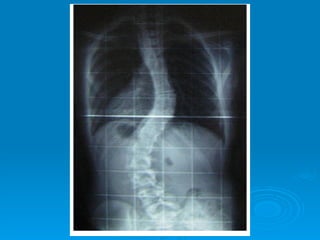

ALTERACIONES DE LACOLUMNA VERTEBRAL •  ESCOLIOSIS: Es cualquier desviación lateral de la columna en el plano frontal. - Leve - Grave - Muy grave Más frecuente en el sexo femenino. Suele aparecer entre los 9 y los 14 años. Escoliosis funcional o actitud Escoliosis estructurada: escoliótica: Ø Zonas afectadas rígidas Ø Zonas afectadas flexibles Ø Acompañada de: Ø Malos hábitos posturales - Acuñamiento vertebral Ø Puede ser corregida - Rotación vertebral

•  ESCOLIOSIS:

Es cualquier desviación lateral de la columna en el plano frontal.

- Leve

- Grave

- Muy grave

Más frecuente en el sexo femenino.

Suele aparecer entre los 9 y los 14 años.